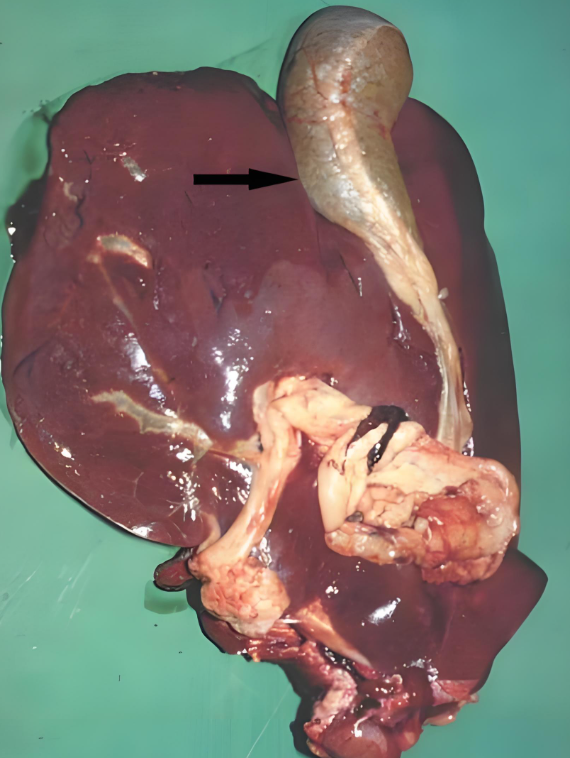

對(duì)牧區(qū)和低洼地帶的養(yǎng)殖戶來(lái)說(shuō),牛羊肝片吸蟲(chóng)病是常年懸著的 “隱患”—— 它不僅是牛羊的 “健康殺手”,導(dǎo)致消瘦、產(chǎn)奶下降甚至死亡,還是人畜共患病,人若生食受污染的水生植物、魚(yú)蝦也可能感染。掌握這種病的 “識(shí)別 - 防控 - 治療” 全流程,是養(yǎng)殖戶減少經(jīng)濟(jì)損失、保障養(yǎng)殖安全的關(guān)鍵。本文結(jié)合臨床實(shí)踐,拆解牛羊肝片吸蟲(chóng)病的科學(xué)應(yīng)對(duì)方案,讓養(yǎng)殖戶能 “看得懂、用得上”。

肝片吸蟲(chóng)病的癥狀分急性、慢性和典型表現(xiàn),不同階段癥狀差異明顯,需針對(duì)性判斷: